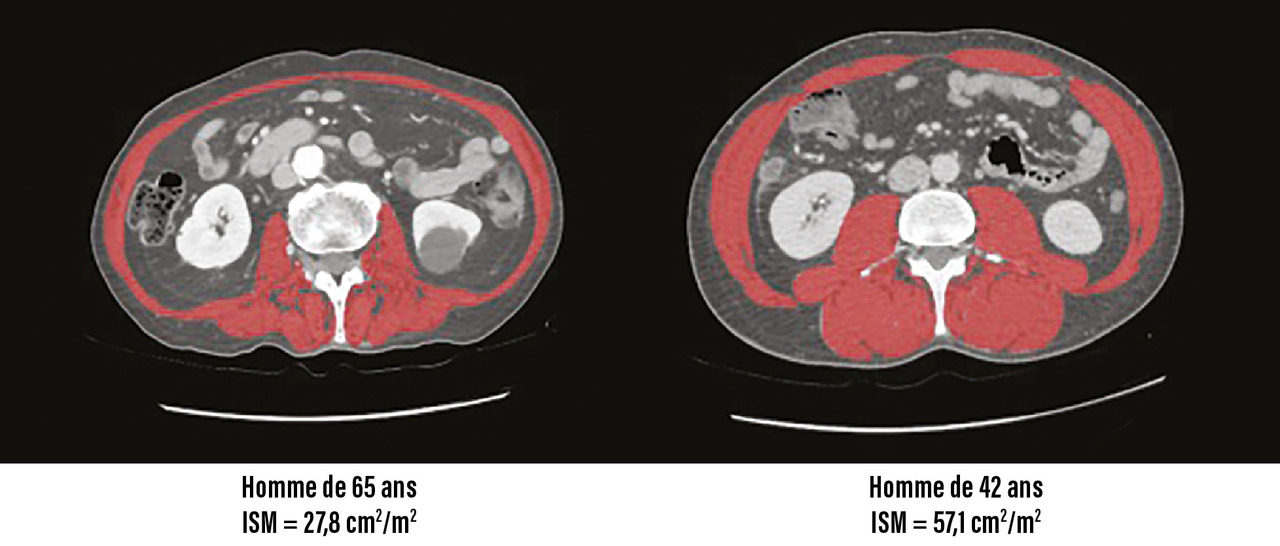

Sur cette coupe, les muscles sont ensuite identifiés à la fois grâce à leur densité et à leur localisation anatomique, ce qui permet de déterminer la surface musculaire (fig. 2). Comme pour l’indice de masse corporelle, il est recommandé de rapporter la surface musculaire à la taille au carré pour obtenir l’indice de surface musculaire (ISM).

La figure 3 met en parallèle les scanners de deux exemples de patients (celui de 65 ans a un ISM abaissé en faveur d’une sarcopénie selon les critères de la HAS 2019 ; les normes pour définir un ISM suffisant sont les suivantes : ≥ 52,4 cm²/m² chez l’homme et ≥ 38,5 cm²/m² chez la femme).